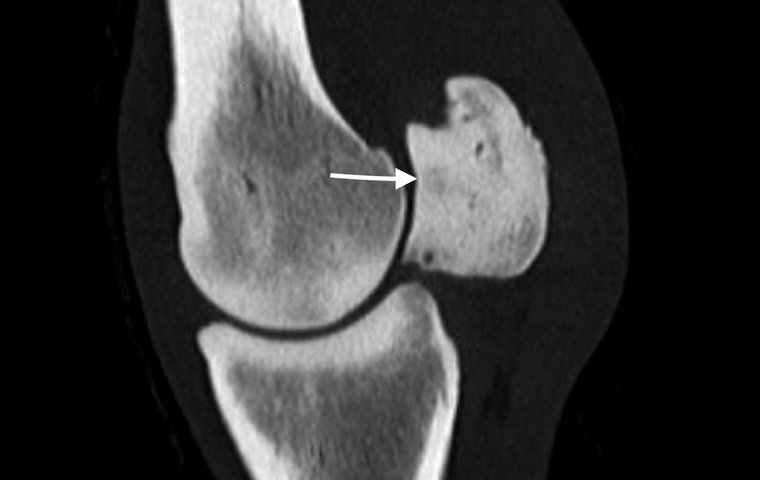

On the first day, an expert panel discussed how diagnostic imaging prior to racing can contribute to risk reduction. This topic was discussed by TRC’s Charles Hayward in a View From The Rail column last year. At the current time, radiography is the most effective tool to identify tiny fractures which will heal effectively, providing exercise is reduced.

Excitingly, technological progress in imaging such as standing MRI, standing CT and PET scanning have the potential to identify pathology even earlier. At this workshop, the expert panel reviewed existing knowledge and discussed how to generate the research evidence that is essential if these novel technologies are to gain a place in effective pre-race risk assessment programmes.